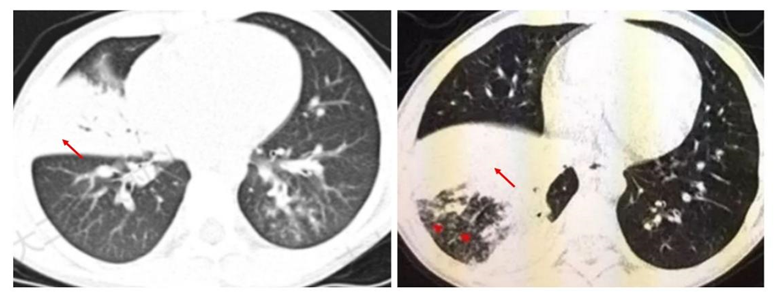

影像学检查尤其是CT是重要的检查手段,也是临床判断病情严重程度和评估预后的主要依据之一。支原体肺炎病理变化是首先侵犯气道粘膜上皮,引起支气管壁水肿增厚,接着向气道周围间质蔓延,引起肺间质充血、水肿及炎性细胞浸润,最后延伸至肺泡。在CT图像上主要有以下几种表现:

4.磨玻璃影:间质内水肿或部分肺泡内渗出,表现为磨玻璃样影。

5.大片实变:表现为中-高密度阴影,可有支气管气象,可伴有肺不张及胸腔积液,早期可表现为小叶中心结节影,随着病灶进展,进展为全小叶或更大范围。

随诊疾病的不同阶段,多种形态、大小不等和密度不均的病灶可混合出现,支气管壁增厚、树芽征、树雾征及实变影等征象可同时存在,结合咳嗽、发热等症状,可对支原体肺炎做出诊断。

肺炎支原体肺炎病灶可先后出现,此起彼伏,临床与影像不同步,往往表现为临床轻、影像重,而且在发病初期支原体抗体阴性或浓度不高,此时也不能排除支原体感染,所以CT在支原体肺炎诊断及评价治疗效果非常重要。